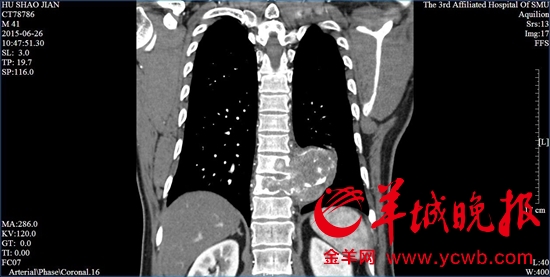

一位患者的脊柱已被肿瘤包围。(图片来源:金羊网)